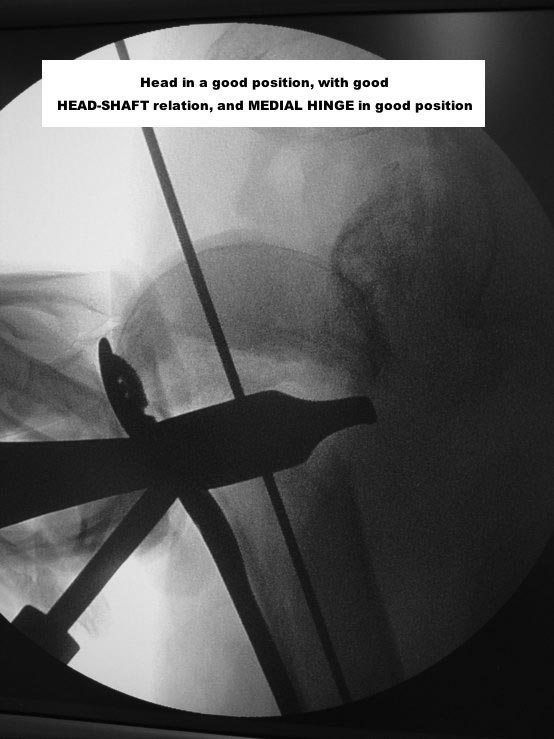

Here are some photos, of chronic, locked, 4 part posterior dislocation, 2 months old, that I did September/2011. Patient is 67, very, very active - had a really reasonable, honest clinical result ...

Photos attached ...